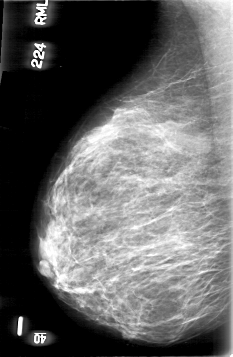

D_4061_1.RIGHT_MLO

RIGHT_MLO LINES 5341 PIXELS_PER_LINE 3481 BITS_PER_PIXEL 12 RESOLUTION 43.5 NON_OVERLAY